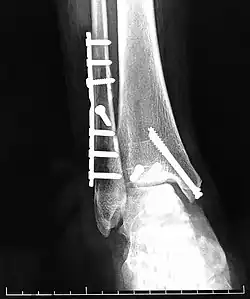

Перелом голени

Переломы голени — патологические состояния, возникающее в ходе нарушения анатомической целостности костей голени человека.